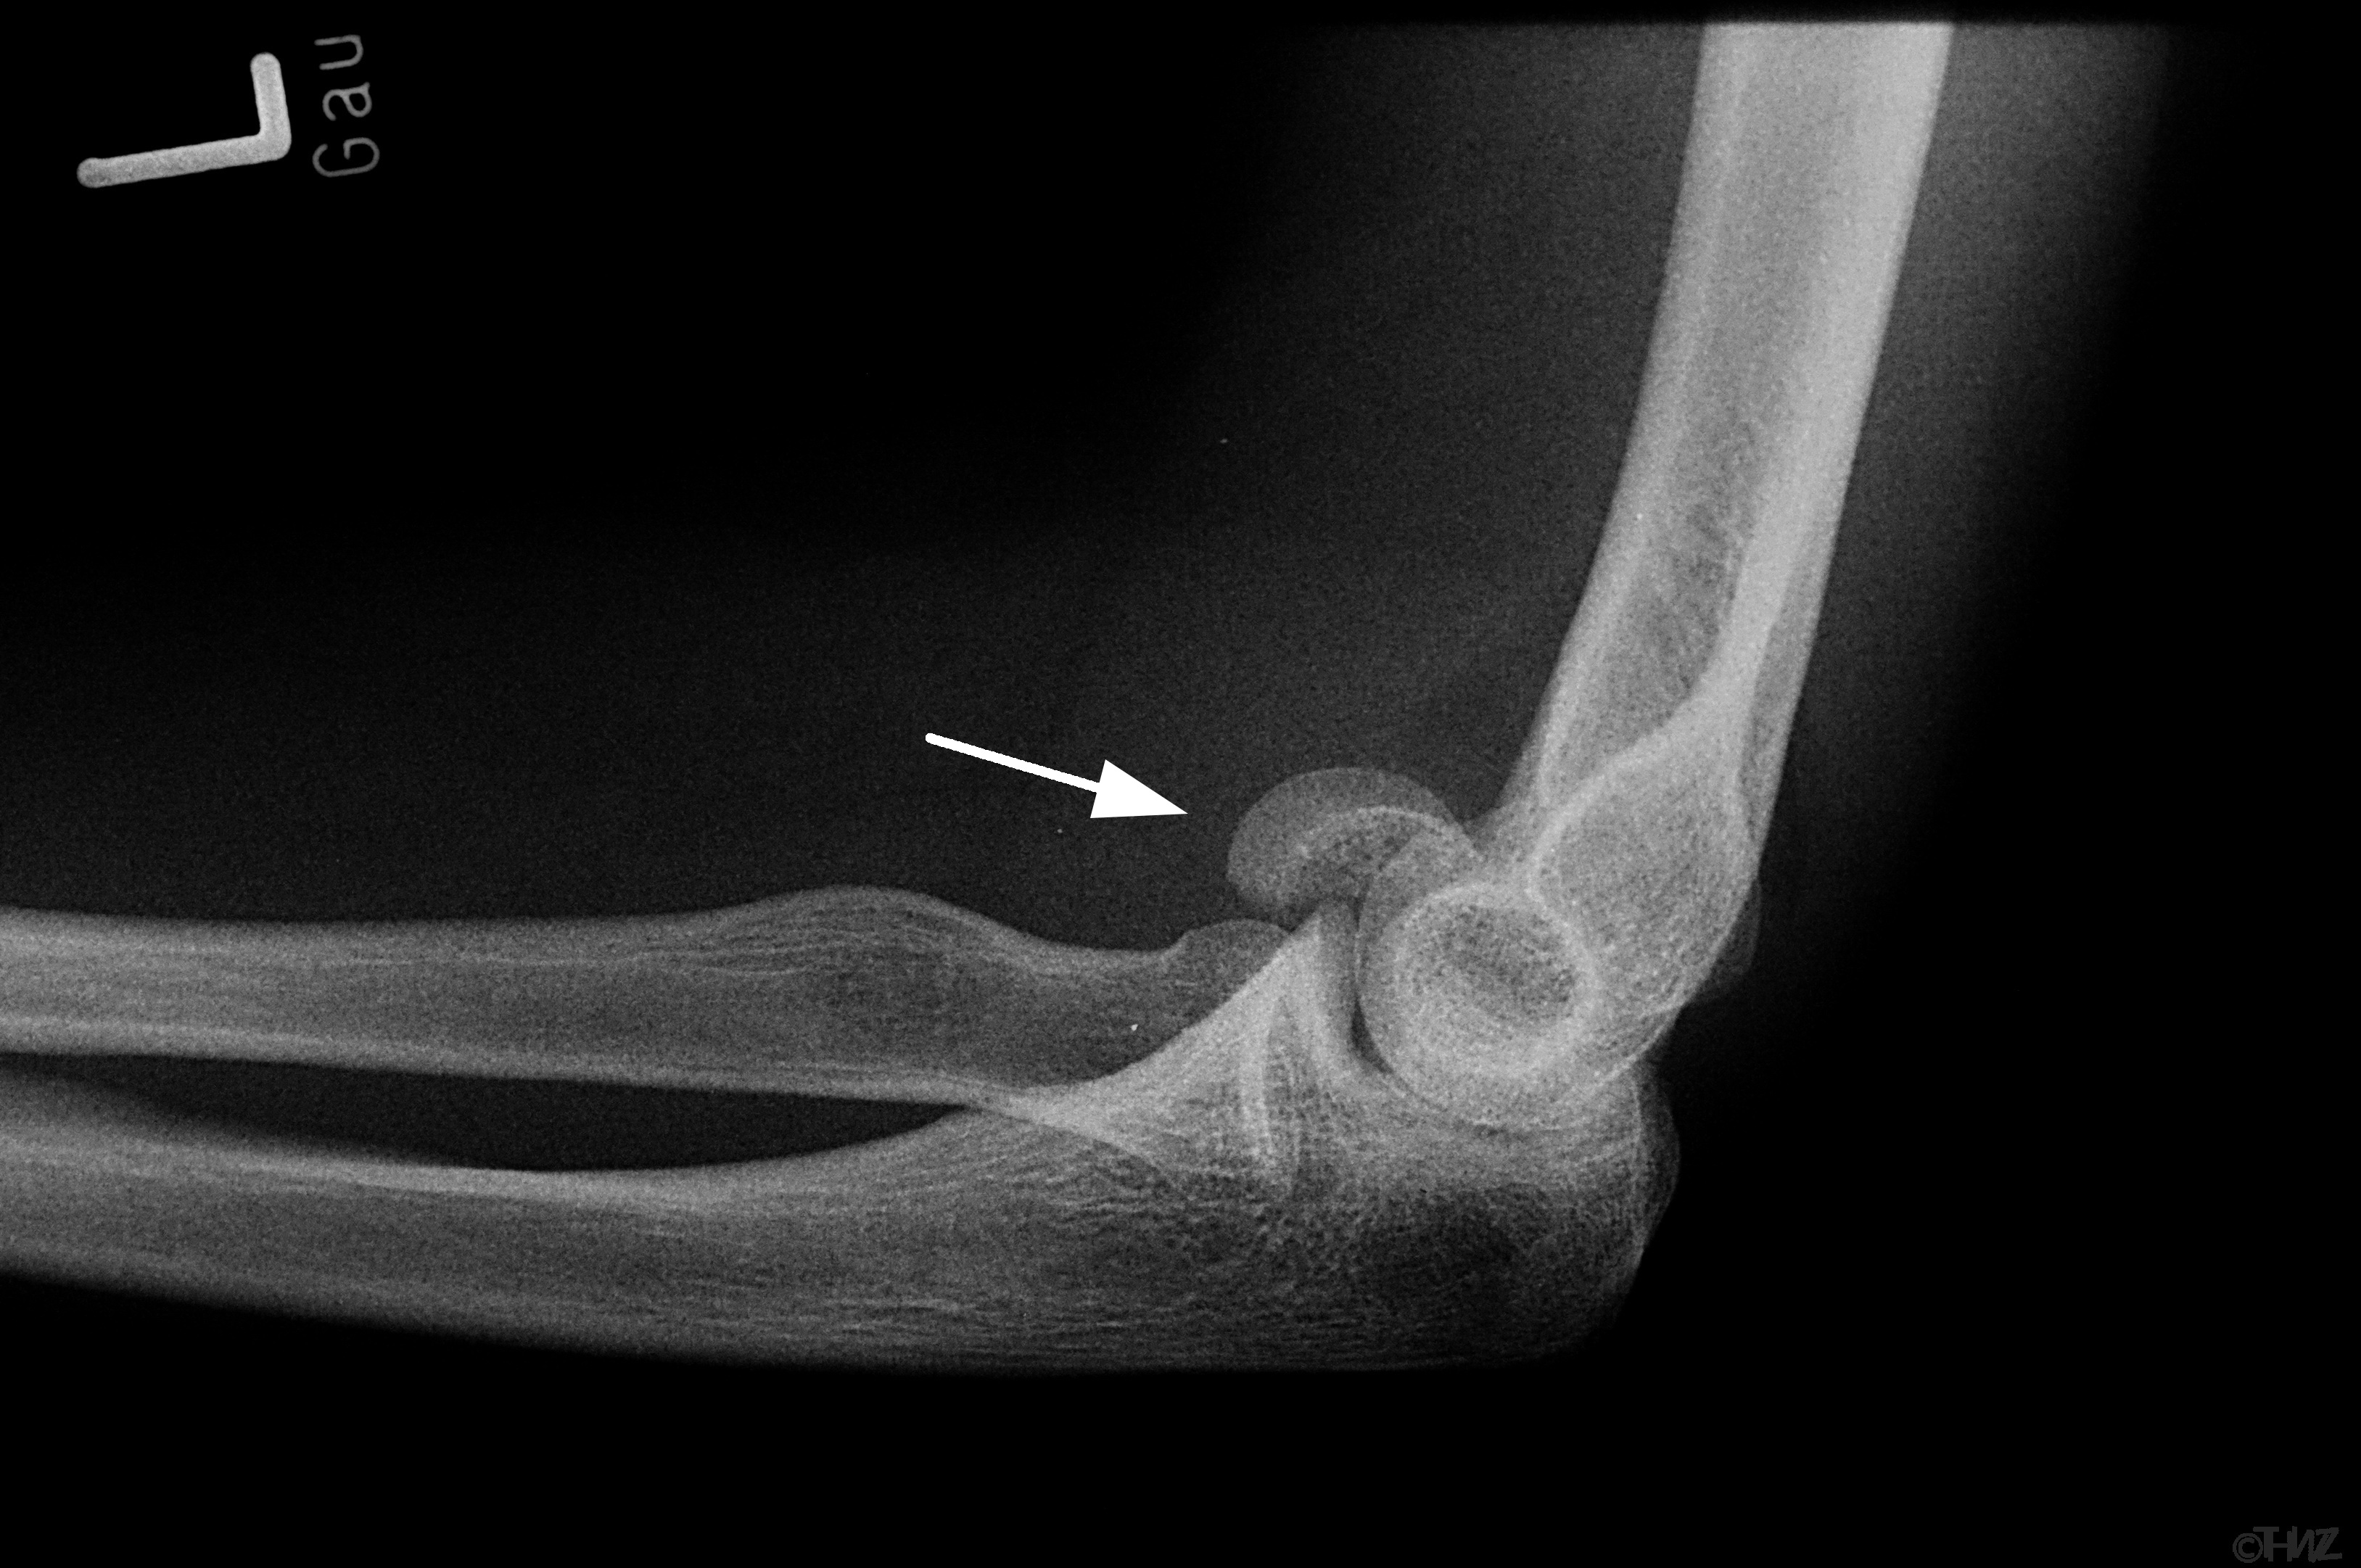

Capitulum humeri fraktur

Bruddet påvises ved en røntgenundersøgelse, men på grund af bruddets placering kan et uforskudt brud være vanskeligt at se ordentligt på almindelige røntgenbilleder, og du skal ofte også have lavet en CT-skanning.